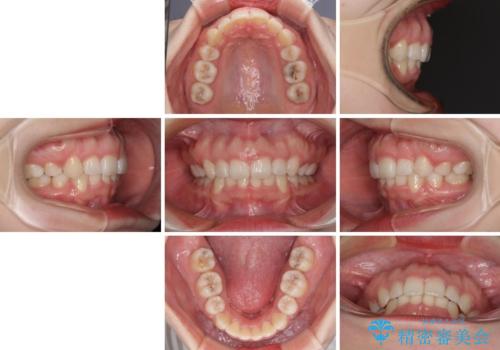

- ハーフリンガル

- 前歯のデコボコと上顎の前突感による口の閉じにくさを気にして来院された患者様です。

目立たない装置を希望されたので、上顎が裏側装置のハーフリンガルを選択し、上下左右の小臼歯(計4歯)を抜歯して矯正治療を行うこととしました。

治療期間の目安は2年半~3年間でしたが、咬み合わせにより上顎装置が頻繁に脱落してしまい、治療期間が長期化してしまいました。

期間はかかったものの、口元の張り出し感や歯のデコボコが解消され、患者様には大変満足していただけました。